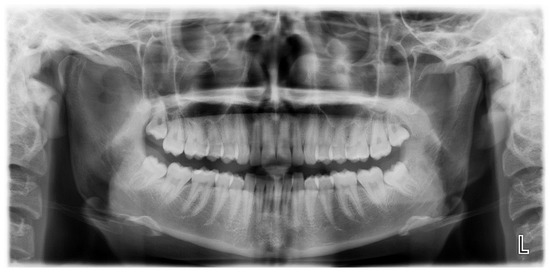

Figure 1.

Patient’s OPG showing no evident anomalies.

A 19-year-old woman was referred to us, presenting with a history of progressive limitation in mouth opening over the previous 18 months. She complained of a dull pain just in front of her right ear, exacerbated by palpation and mandibular movements. She had no medical history and did not report any previous local trauma. She was initially diagnosed with temporomandibular disease (TMD) dysfunction and treated conservatively with an occlusal bite with no symptomatologic relief. At physical examination, the maximum mouth opening (MMO) was reduced to 25 mm, but mandibular movements were preserved. No articular noises during temporomandibular joint (TMJ) bilateral palpation were perceived, but she complained of pain in the masticatory muscles bilaterally. No malocclusion, facial asymmetry or swelling were identified. The orthopantomogram (OPG) (Figure 1) and the magnetic resonance imaging (MRI) were negative. Given the absence of clinical improvement but a rather slow and progressive reduction in MMO, a computed tomography (CT) was performed, revealing an enlargement and an abnormally shaped right CPM, establishing a close relationship with the zygomatic arch (Figure 2). Furthermore, single-photon emission computed tomography (SPECT) was prescribed, and the late images of bone uptake showed a focal increase in the correspondence of the so-called pseudojoint between the jaw and the right zygomatic bone compared to the left side (Figure 3). According to this, a provisional diagnosis of JD was made. The patient underwent a right coronoidectomy through an intraoral approach under general anesthesia with awake, blind, nasal intubation. The right, mushroom-shaped coronoid process was identified and resected, and a sort of fibrotic capsule between the inner aspect of the zygoma and the CPM was highlighted, establishing the pseudojoint, with this confirming the diagnosis of JD (Figure 4). Histopathologically, the specimen showed a growth pattern of hyperplastic bone tissue covered by cartilaginous layers and an external coating of dense fibrous tissue. There were no intra-operative or immediate postoperative complications. Postoperative CT was obtained for baseline follow-up. The MMO increased to about 30 mm in the immediate postoperative period, and this improved to 40 mm after a month of aggressive physiotherapy. She underwent clinical and radiological follow-up, and after 12 months, the MMO was stable, and no recurrence was observed.

The diagnosis of JD is also often delayed because an OPG does not always permit suspecting a CPM enlargement, and the reported symptoms push the clinician to request an MRI with TMJ scans, which do not permit a proper CPM visualization. CT is frequently the last radiological examination performed. Multiplanar CT and 3D CT reconstructions, as well as VSP (Mimics, Materialise NV, Leuven, Belgium), represent the most effective tool for the correct diagnosis and surgical planning of JD cases. The definitive treatment of JD is surgical. Those submitted to surgery are patients that obviously cannot open their mouths properly, and this also entails anesthesiological issues, such as often having to resort to awake intubation or the use of a fibroscope. We saw that, despite this, in 66 cases (56.9%), the coronoidectomy was performed by an intraoral approach, while an extraoral approach was used 32 times (27.6%), and a combined approach was used 12 times (10.3%). This analysis shows slight differences in the rates reported in the literature but a significant 10% increase in the percentage of intraoral coronoidectomies previously reported [7]. Despite the difficulty of operating in such a confined space, made even more uncomfortable by the pathology, the intraoral approach is nevertheless preferred because of its relative lack of possible complications (almost no risk for facial nerve injury), such as eliminating surgical skin scars and a good possibility to reach the abnormal CPM. This approach can be implemented by various mini-invasive techniques, primarily endoscopy [115]. Other authors propose different approaches, such as coronal, hemi-coronal or trans-zygomatic [62,64]. In grade 1 cases, a conservative attitude can be taken into account, and surgery may be postponed depending on the rate of worsening of the MMO or radiological changes. In grade 2 and 3 patients, in our opinion, surgery should be considered in the first instance. We did not highlight any significant difference in MMO post-treatment, which resulted in 40.2 mm overall (20–64 mm), between patients treated via an intraoral approach (38.2 mm; 20–61 mm), extraoral (42.6 mm; 28–55 mm) and combined approaches (44.3 mm; 35–64 mm). A parameter that would be interesting to evaluate is the follow-up of these patients in order to verify any radiological or clinical recurrence. Unfortunately, in only 41 (35.3%) out of the 116 cases are the follow-up periods reported, with an average of 17.4 months. Regarding this, only two cases of recurrence (1.7%) were highlighted in our review—a percentage in line with what is reported in the literature [4]. However, it should be noticed, as it was in the case of follow-up, that no explicit mention was made about the future fate of the patients in 92 (79.3%) of the cases examined.